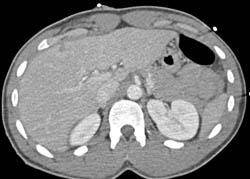

Bleed in and Near Liver S/p Stab Wound